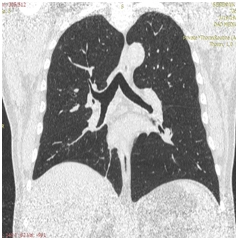

КТ ОГП 06.01.2017. КТ-картина внутрипросветного патологического мягкой плотности компонента (центральный рак?) в промежуточном бронхе правого легкого с ателектазом нижней доли. Лимфаденопатия правого корня, количественная лимфаденопатия средостения.